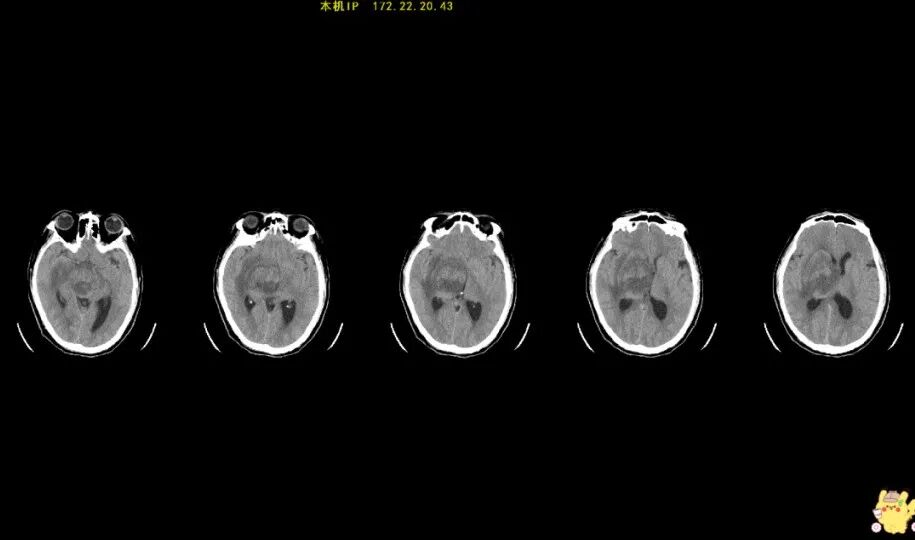

病例一:18歲,男性患者,因左上肢麻木、抽動(dòng)、癲癇發(fā)作入院,磁共振檢查提示右側(cè)額葉腫瘤。

病例二:40歲,男性患者,因頭痛三個(gè)月入院,被診斷為顱內(nèi)腫瘤。

病例三:45歲,女性患者,因反復(fù)頭痛一周入院,MR提示顱內(nèi)腫瘤,手術(shù)治療后病理結(jié)果為腦膜瘤。

病例四:57歲,男性患者,因左側(cè)肢體乏力3周入院,被診斷為腦內(nèi)腫瘤。